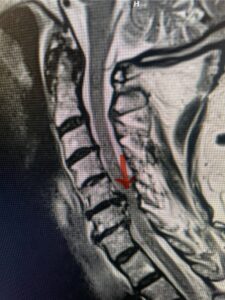

Another patient, a 77 year-old female, presents with pain, numbness, and weakness of her arms and difficulty with balance over a 6-month period. MRI revealed severe osteophytic disease at C5-C7 with cord compression (Fig. 4). Further work-up by fine-cut cervical CT to evaluate the nature of compression revealed a completely calcified osteophyte (Fig. 5). Although the patient had a good lordosis and a posterior cervical approach would accomplish an adequate decompression, we elected to perform a two-level anterior cervical discectomy and fusion. This particular osteophyte is formidable because of its size but the compression was all anterior and would be a less invasive approach. Fortunately, during the procedure, the patient had a fair amount of osteoporosis which allowed the osteophyte to be drilled and bit away with considerable ease. Interestingly, the C6 7 osteophyte which was more a sheet of osteophyte was more challenging to remove. In the end the decompression went well, and we placed two interbody devices filled with bone graft with plates at each level (Fig. 6). The patient had a nice recovery with immediate reduction of pain and numbness. This case demonstrates the importance of recognition of cervical myelopathy in its early stages. A significant reversal of function is generally the rule if the patient has appropriate correlative findings on exam and MRI, particularly with long tract distribution weakness development within a year time period.

Figs 4a: Sagittal and axial T2-weighted cervical MRIs demonstrating large osteophyte worse at C5-6 compressing spinal cord more eccentrically to the left (red arrows)

Fig 5a: Sagittal and axial cervical fine-cut CT scan demonstrating severe osteophyte formation causing cord compression at C 56 (red arrow)

Fig 5b: Sagittal and axial cervical fine-cut CT scan demonstrating severe osteophyte formation causing cord compression at C 56 (red arrow)